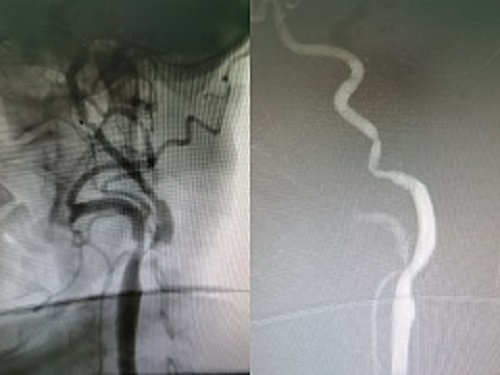

下图为该女性患者血管闭塞的造影成像:由于血管闭塞/狭窄,得不到血液的供应,让这颗“大树”拥有了“小蛮腰”。

下图是该女性患者拥有“小蛮腰”(左)与撑开“小蛮腰”(右)的供血彩色图像,恢复供血的血管正将营养物质和氧气输入,枯竭的“树枝”因为得到了血液的灌溉,焕发着新的生机。让人仿佛看到了早春的嫩绿,生机盎然。术后的陈女士恢复良好,告别了依赖家人的生活,说话流畅,右侧肢体行动自如,生活完全恢复自理,笑容再次展现在了陈女士的脸上。